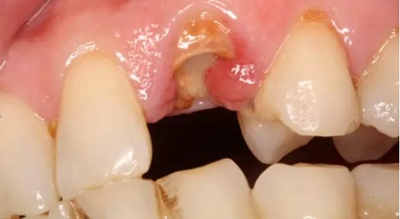

患者女性,55歲,3年前B3纖維樁+鑄瓷全冠修復,一周前牙冠折斷,就診后,發(fā)現(xiàn)纖維樁根管口處折斷,周圍牙齦增生,建議患者行冠延長手術。首先去除斷端的纖維樁。拍片示牙根長度充足。于是開始冠延長手術。

因為是前牙,故該患者將來修復體邊緣必須為齦下,所以3個月后再行修復。以下為手術前照片。